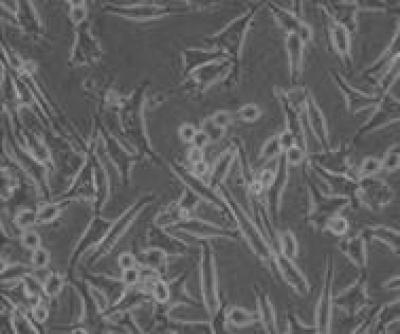

The effects of Amyloid beta (Aβ)-Aβ-binding alcohol dehydrogenase (ABAD) may exacerbate Alzheimer's disease pathology. Therefore, blocking Aβ-ABAD-mediate effects with ABAD decoy peptide (ABAD-DP) may be a potential therapeutic strategy for Alzheimer's disease. Dr. Jiang Wu and team from the First Hospital of Jilin University in China successfully constructed a recombinant adenovirus constitutively secreting and expressing Aβ-ABAD decoy peptide (rAAV/ABAD-DP-6His). Their results showed that rAAV/ABAD-DP-6His increased superoxide dismutase activity in hydrogen peroxide-induced oxidative stress-mediated injury of PC12 cells. Moreover, rAAV/ABADDP-6His decreased malondialdehyde content, intracellular Ca2+ concentration, and the level of reactive oxygen species. rAAV/ABAD-DP-6His maintained the stability of the mitochondrial membrane potential. In addition, the ATP level remained constant, and apoptosis was reduced. Overall, the experimental findings, published in the Neural Regeneration Research , indicate that rAAV/ABAD-DP-6His generates the fusion peptide, Aβ-ABAD decoy peptide, which effectively protects PC12 cells from oxidative stress injury induced by hydrogen peroxide, thus exerting neuroprotective effects.